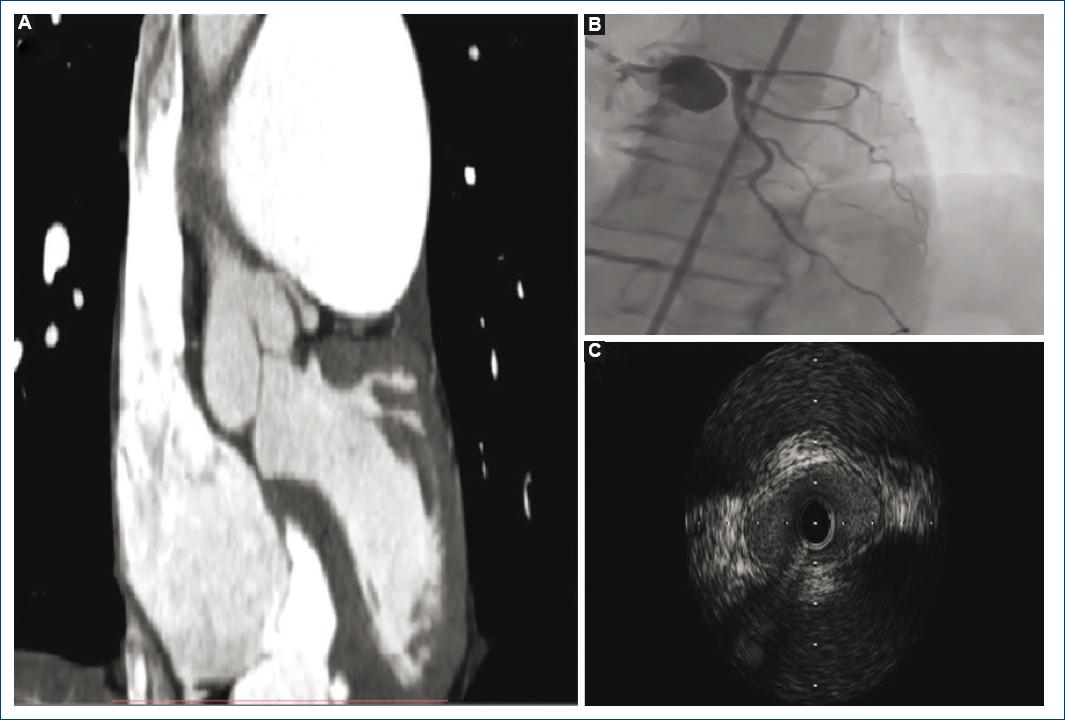

Se describe el caso de una paciente de sexo femenino, de 56 años de edad, con diagnóstico de hipertensión pulmonar idiopática tres años antes de la consulta, quien a su ingreso refirió disnea y dolor precordial de características anginosas en clase funcional III de dos semanas de evolución. Al ingreso se confirmaron signos clínicos de insuficiencia cardíaca derecha (edemas en miembros inferiores, leve derrame pleural bilateral, reflujo hepatoyugular positivo), aumento de la intensidad del segundo ruido cardíaco a expensas del componente pulmonar y soplo expulsivo en foco pulmonar. El estudio diagnóstico inicial incluyó un electrocardiograma con hipertrofia ventricular derecha y bloqueo completo de rama derecha. El ecocardiograma Doppler evidenció dilatación de cámaras derechas con depresión leve de la función sistólica del ventrículo derecho y una insuficiencia tricuspídea moderada con una velocidad pico de 4.52 m/s, una presión sistólica de la arteria pulmonar calculada de 90 mmHg (con base en los 82 mmHg de gradiente entre ventrículo y aurícula derecha sumados a los 8 mmHg de presión en la aurícula derecha determinados a partir del diámetro y colapso de la vena cava inferior). De manera adicional, este método posibilitó la sospecha de la compresión extrínseca del tronco de la coronaria izquierda como causa de angina al hallar una dilatación grave del tronco de la arteria pulmonar (55 mm), así como de sus ramas principales1. Ante dicha sospecha se indicó una angiotomografía de tórax que confirmó la marcada dilatación de la arteria pulmonar (54 mm en este caso por este método) y delineó el trayecto anormal del tronco de la coronaria izquierda, con marcada reducción de su luz, disminución de la distancia entre éste y la arteria pulmonar y con la formación de un ángulo muy estrecho entre él y el seno de Valsalva izquierdo (Fig. 1A)2. Tras asumir la compresión extrínseca por parte de la arteria pulmonar, se realizó con fines diagnósticos iniciales y potencialmente terapéuticos una coronariografía que mostró obstrucción grave del tronco de la coronaria izquierda a nivel ostial, con flujo de la escala de TIMI (thrombolysis in myocardial infarction) 3 y un trayecto casi paralelo a la pared del seno de Valsalva izquierdo por el desplazamiento generado por la compresión (Fig. 1B). Para una mejor definición de la lesión se utilizó ultrasonido intravascular durante el procedimiento, que registró la ausencia de placas de ateroma y confirmó la deformación de la luz de perfil elíptico, la reducción crítica del diámetro arterial a nivel ostial y la naturaleza puramente extrínseca de la obstrucción (Fig. 1C)3. A continuación se decidió el implante de un stent liberador de fármaco de 4.5 x 20 mm en el tronco de la coronaria izquierda, sin complicaciones. La paciente evolucionó de modo favorable y se realizó un seguimiento anual con angiotomografía de tórax sin evidencias de complicaciones a tres años del implante.

Figura 1 A: angiotomografía de tórax, reconstrucción coronal: marcada dilatación de la arteria pulmonar con estrecho espacio entre ésta y el seno de Valsalva, lo que modifica el trayecto del tronco de la coronaria izquierda. Nótese el ángulo muy agudo entre el seno de Valsalva y el tronco de la coronaria izquierda, con reducción de la luz de este último. B: coronariografía: grave estrechez del tronco de la coronaria izquierda desde su nacimiento. El resto del árbol coronario izquierdo no muestra lesiones significativas. C: ultrasonido intravascular: se descarta la presencia de placas ateroescleróticas. Se observa la deformación de la luz del tronco de la coronaria izquierda que se torna inicialmente elíptica por compresión hasta hacerse mínima (2 mm²).

En pacientes con diagnóstico de hipertensión pulmonar, la angina de pecho es un síntoma de frecuente aparición, referido por el 35 a 40% de todos los pacientes con esta enfermedad4. Su aparición se ha atribuido por lo general al desequilibrio metabólico generado por la hipertrofia y la sobrecarga del ventrículo derecho más que al compromiso coronario5. Sin embargo, la compresión extrínseca del tronco de la arteria coronaria izquierda por la dilatación de la arteria pulmonar principal es una entidad cada vez más reconocida como causa de este síntoma, con un prevalencia notificada cercana al 40% en pacientes portadores de hipertensión pulmonar que refieren angina o equivalentes anginosos6. Esta complicación mecánica es tratable, pero en ausencia de resolución puede tener consecuencias graves como el infarto agudo de miocardio, la disfunción ventricular izquierda, las arritmias cardíacas, e incluso la muerte súbita, por lo que es una entidad de interés clínico relevante7. Con respecto al tratamiento, las alternativas posibles son la operación de revascularización miocárdica y la angioplastia percutánea. Si se considera el alto riesgo quirúrgico que presentan habitualmente los pacientes portadores de hipertensión pulmonar, hoy en día se prefiere la revascularización a través de procedimientos percutáneos, con la colocación de stents8. No existe evidencia clara sobre cuál es el tipo de stent que debe utilizarse (convencional o liberador de fármaco), por lo que la decisión debe tomarse con base en el riesgo hemorrágico del paciente intervenido, con uso de stents convencionales en aquéllos con alguna predisposición al sangrado o con necesidad de tratamiento anticoagulante por otro motivo, para reducir al mínimo los tiempos del doble tratamiento antiagregante6.